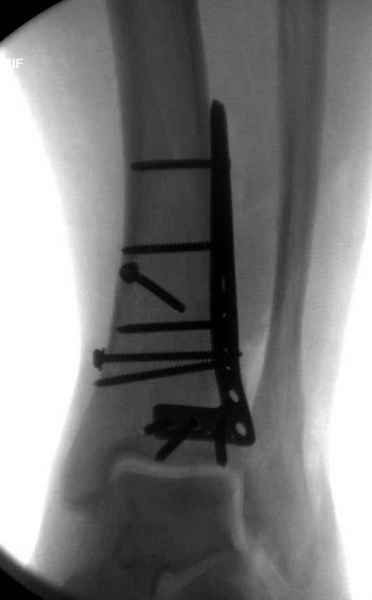

Публикации за последние пять лет показывают, что в лечении переломов

пилона важным является состояние мягких тканей. Поэтому при лечении

пилона, особенно после высокоэнергетической травмы, необходимо

придерживаться правила - лучше проводить запоздалую фиксацию, чем после

операции иметь проблемы с мягкотканными осложнениями.

Закрытый метод фиксации рекомендуется, когда фрагменты были сопоставлены

в результате лигаментотаксиса, а открытый минимальный метод при

нерепонированных отломках.

После ExFix проведение компьютерной томографии считаем обязательным,

получаем информацию о расположении  крупных фрагментов, которая

подскажет сторону операционного доступа и направления проведения

фиксирующего материала.

Любая фиксация - преконтурированные пластины с уголовой стабильностью,

медиальная, латеральная в зависимости от нахождения отломков или

наружная фиксация типа аппарата Илизарова подходят для ранней мобилизации.

Не все переломы пилона фиксируются медиальной

пластиной,  поэтому, учитывая что большой фрагмент

находится на латеральной стороне, я бы применил

передне-латеральную пластину.